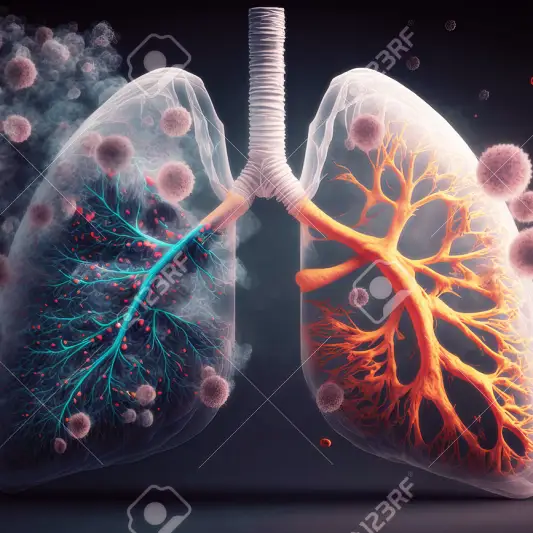

폐암의 주요 원인 중 하나는 담배피우기입니다. 흡연은 폐암 발생의 주요한 원인으로 알려져 있으며, 흡연자들의 폐암 발생 위험은 비흡연자보다 상당히 높습니다. 그러므로 흡연을 피하는 것이 가장 확실한 예방 방법입니다.

뿐만 아니라, 실내와 실외의 공기 오염도 폐암 발생 위험을 높입니다. 미세먼지, 공업 배기가스 등으로 오염된 공기를 계속해서 흡입하면 폐암 발생 가능성이 크게 증가할 수 있습니다. 따라서 실내에서 공기 청정기를 사용하거나, 실외에서는 마스크를 착용하는 것이 폐암 예방에 도움이 됩니다.

또한, 폐암의 조기 발견은 생존율을 크게 높일 수 있습니다. 폐암은 초기에는 증상이 거의 없어서 잘 알려지지 않았습니다. 그러나 최근에는 폐암 스크리닝 검사의 중요성이 부각되어 많은 사람들이 해당 검사를 받고 있습니다. 폐암 스크리닝은 폐의 암세포를 조기에 발견하여 치료할 수 있는 기회를 제공해줍니다.